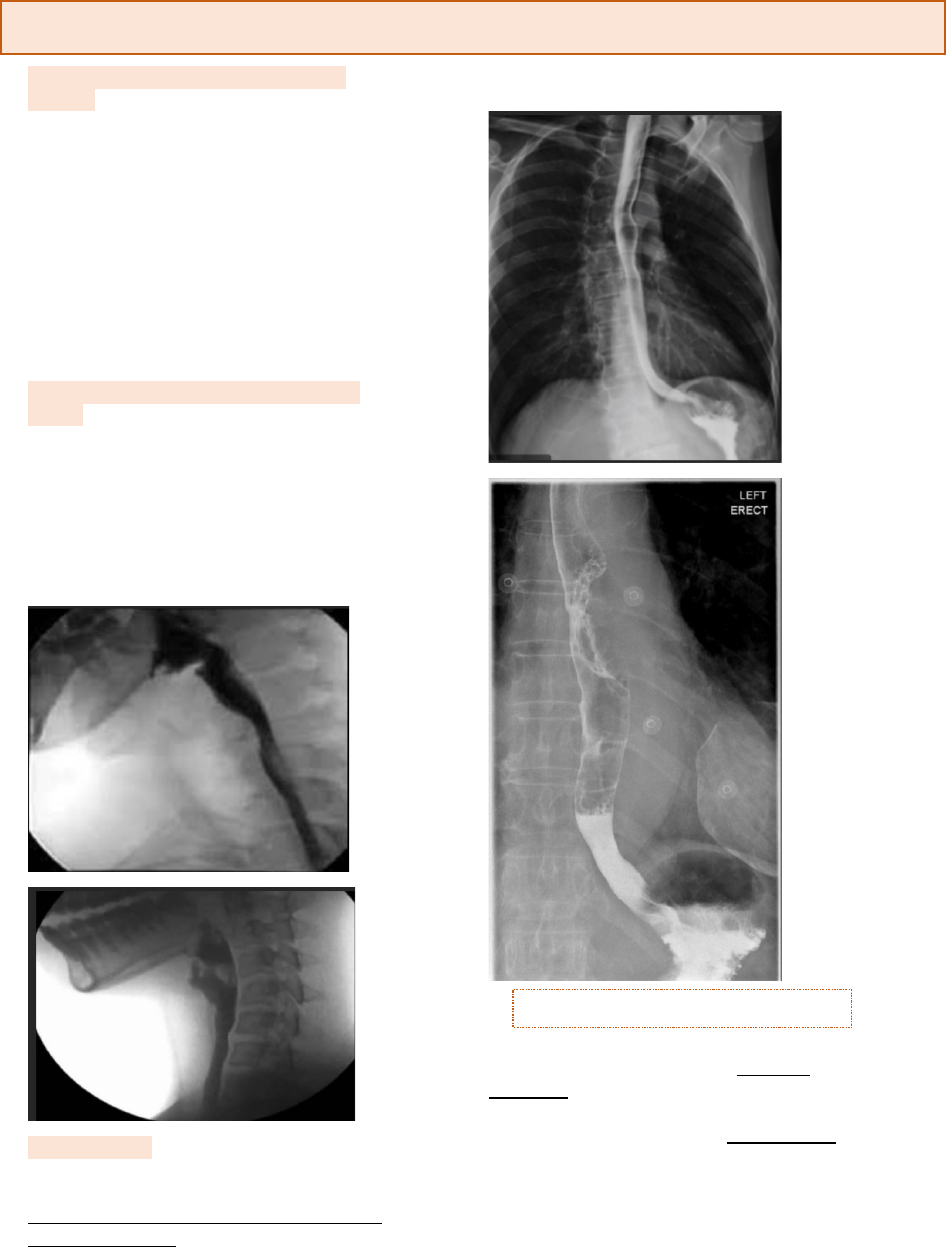

Acalasia

• Junção esôfago gástrica, a função do esfíncter é quando o alimento chega no estomago ele contraia e impeça que o alimento volte, no paciente que tem acalasia a contração fica constante e o alimento tem dificuldade de passar, lúmen bem estreitado. Ao longo do tempo dilata a porção distal do esôfago e a parede hipertrofia até entrar em falência (perde mobilidade), megaesôfago

• É um distúrbio da motilidade esofágica caracterizada pela ausência de peristalse esofágica e alteração do relaxamento do esfíncter inferior do esôfago (EIE) em resposta à deglutição, levando à uma obstrução funcional da junção esôfago-gástrica, e que a longo prazo vai levar à dilatação esofágica conhecida como megaesôfago

Bico de papagaio (hipertrofia da válvula fazendo um estreitamento da luz, paredes espessadas – começa no grau III

• Alterações semelhantes a acalasia - Parte distal contrai, e forma uma dilatação montante, afilamento da porção distal e dilatação do corpo, formando um balão